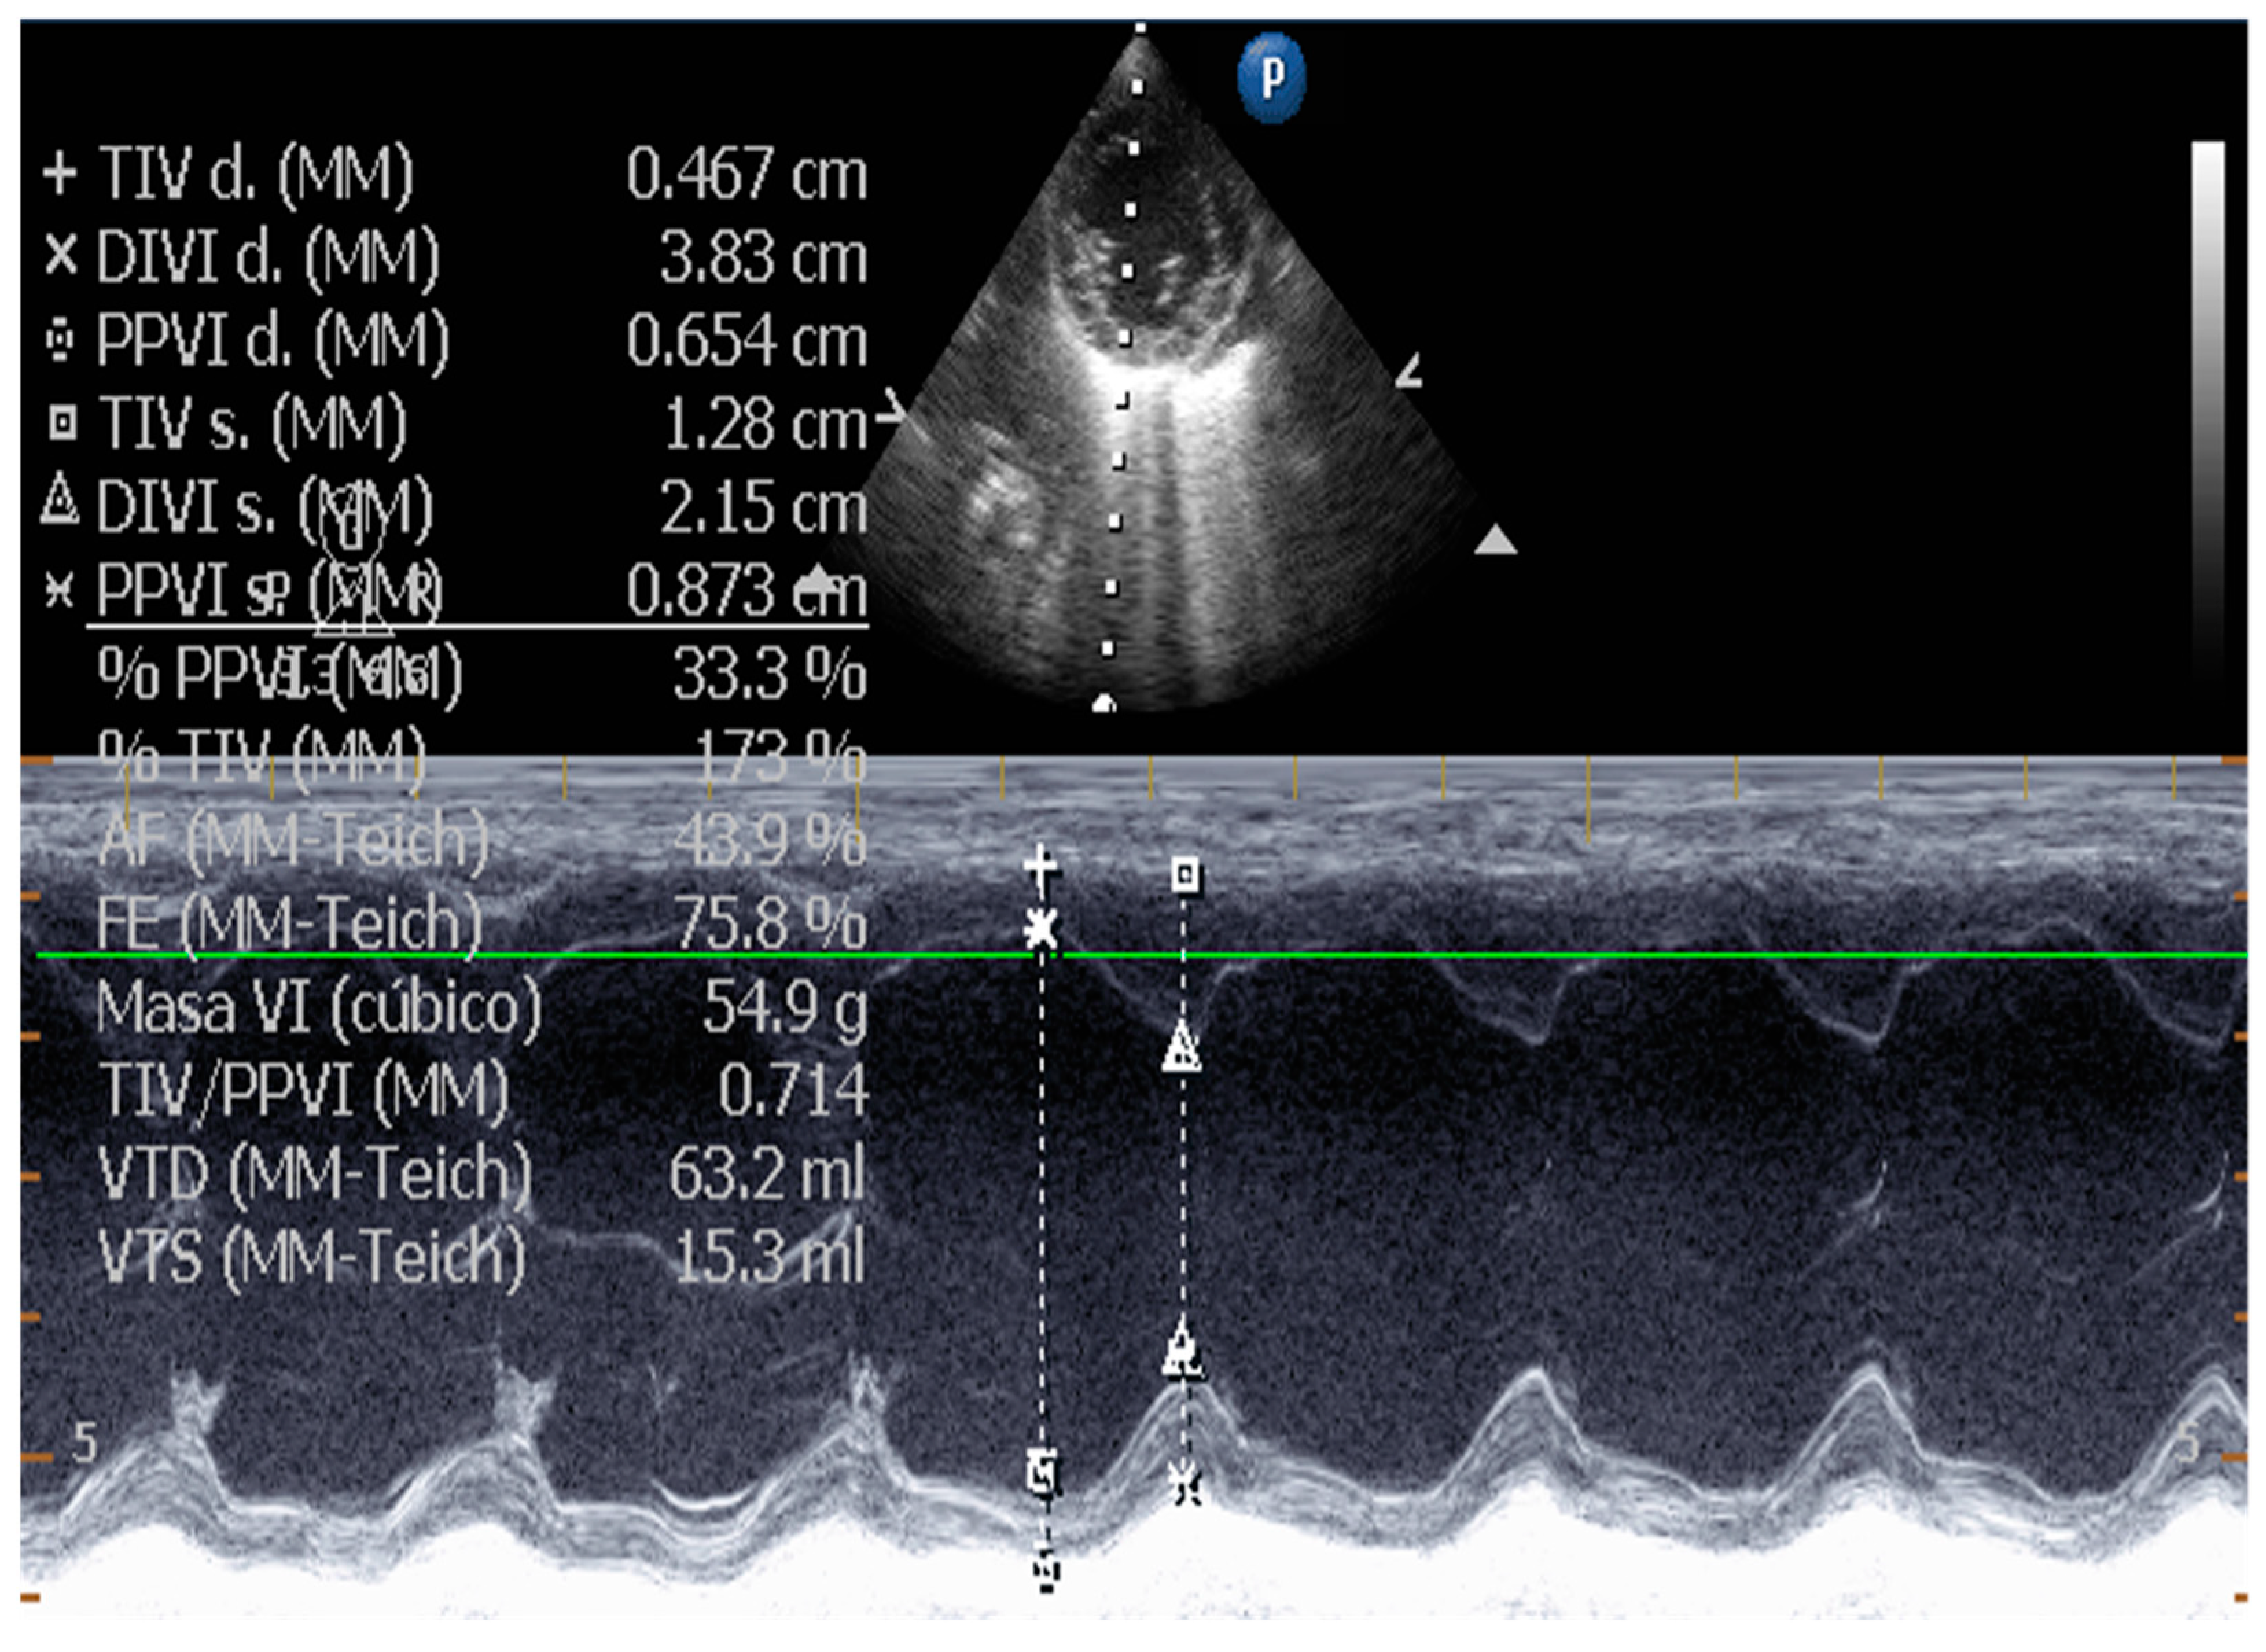

5.1.1. Measurement of Left Ventricular Volume by Simpson’s Method of Disks and Left Ventricular M-Mode

| Measurement of Left Ventricular Volume | M-mode echocardiography is widely used in canine cardiology, but its utility is debated. American Society of Echocardiography recommends against using linear measurements in the human patient. SMOD is recommended [100,102,103]. |